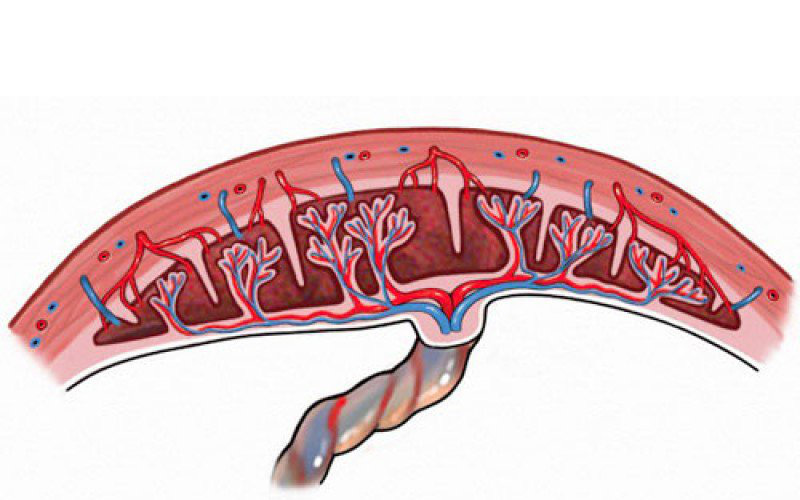

Thông thường, sau khi vượt cạn, bánh nhau sẽ ự động tách khỏi thành tử cung và đẩy ra ngoài. Tuy nhiên, không ít trường hợp bị nhau cài răng lược.

Nhau cài răng lược được định nghĩa là tình trạng một phần hoặc toàn bộ bánh nhau bám chặt và không thể tách rời khỏi thành tử cung, thậm chí có thể xâm lấn các cơ quan xung quanh. Nhau cài răng lược rất nguy hiểm, bởi vì đây là nguyên nhân gây ra các tình trạng như băng huyết sau sinh, rối loạn đông cầm máu, hậm chí gây tử vong cho sản phụ.

Dựa trên mức độ xâm lấn của bánh nhau, nhau cài răng lược có thể phân chia thành 3 thể chính:

- Accreta: Đây là thể nhẹ. Ở thể này, bánh nhau bám trực tiếp lên bề mặt tử cung. Theo các thống kê, thể Accreta chiếm khoảng 79% các trường hợp nhau cài răng lược

- Increta: Đây là thể trung bình. Ở thế Increra, bánh nhau xâm nhập sâu vào trong cơ tử cung nhưng chưa qua khỏi lớp thanh mạc tử cung. Thể này chiếm khoảng 14% các trường hợp bị nhau cài răng lược.

- Percreta: Đây là một thể nặng. Theo đó, bánh nhau xâm lấn xuyên qua lớp thanh mạc tử cung và xâm lấn đến những cơ quan lân cận như ruột hay bàng quang. Thể này chiếm khoảng 7% các trường hợp.

Nhau cài răng lược được phận chia thành 3 thể từ nhẹ tới nặng - Ảnh Internet.